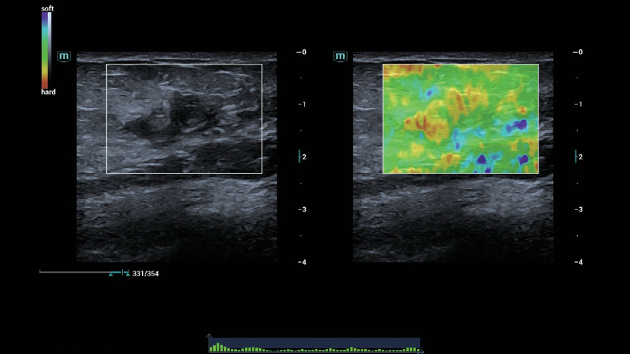

ZST+ ??? ???? ?? ???

ZST+ ???? ???? ??? ???? ??? ?????. ??? ???? ?? ? ???? ?? ??? ?? ??? ?????. ??? ??? ? ?? ??? ??? ???? ?????? ??? ???? ???? ??? ?? ?? ?? ?? ???? ?? ??? ?? ??? ?????.